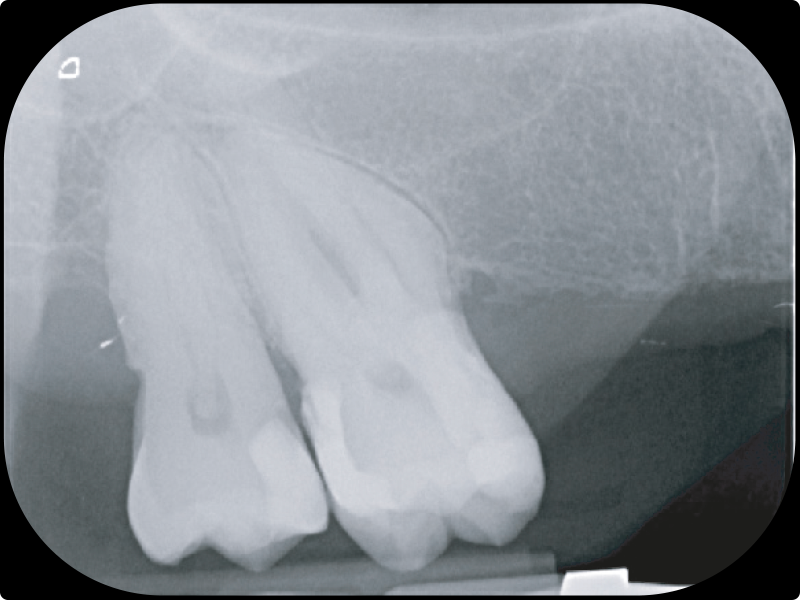

• Gestione dei canali calcificati e curvi:

• come evitare gli errori e raggiungere gli obiettivi